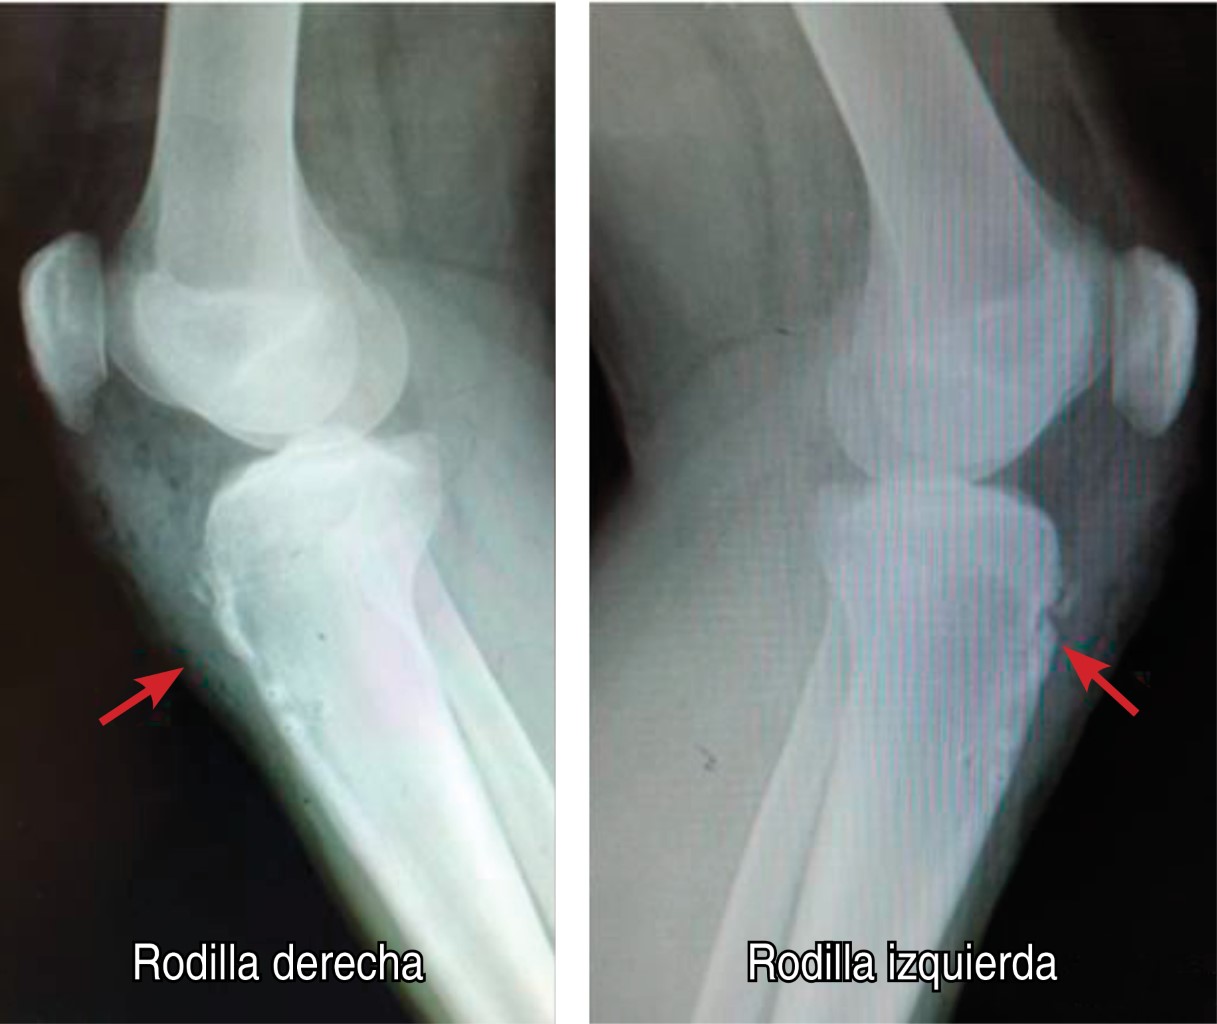

Evaluación radiográfica con fractura de tuberosidad tibial Ogden IIA, para ambas rodillas (Figura 1). Se descarta por análisis laboratorial deficiencia de vitamina D o alguna otra alteración endocrinológica. Se aplican criterios de Beighton-Horan descartando síndrome de hipermovilidad o alguna otra afección de la colágena.

Figura 1